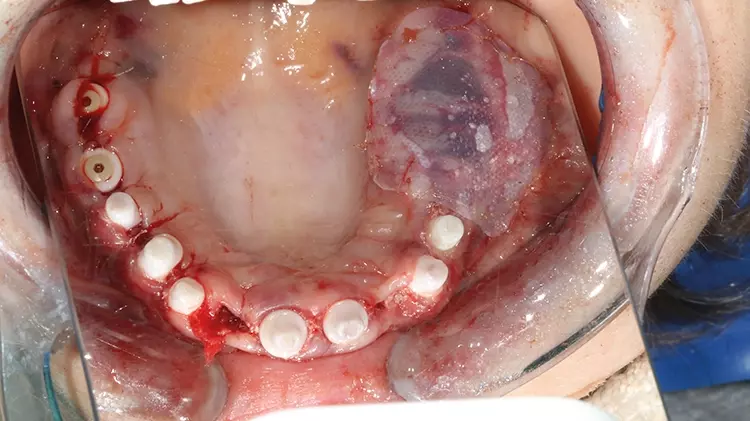

Im weiteren Behandlungsverlauf wurde die Patientin bei einem anderen Vorbehandler bereits festsitzend mit Titanimplantaten versorgt, welche jedoch aufgrund starker lokaler (Schmerzen, Entzündungen) sowie systemischer Reaktionen (u. a. Haarausfall, Hautausschläge) wieder entfernt wurden. Zum Zeitpunkt der Erstvorstellung der folgenden Behandlungsdokumentation war der Restzahnbestand nur noch auf die vier OK-Frontzähne und drei UK-Frontzähne mit voranschreitender Kieferatrophie beschränkt (Abb. 2 und 3).

Abb. 2: Z. n. multiplen Zahnextraktionen alio loco / Zustand bei Erstvorstellung. SDS

Abb. 2: Z. n. multiplen Zahnextraktionen alio loco / Zustand bei Erstvorstellung.

Abb. 3: Z. n. multiplen Zahnextraktionen alio loco / Zustand bei Erstvorstellung. SDS

Abb. 3: Z. n. multiplen Zahnextraktionen alio loco / Zustand bei Erstvorstellung.

Der Restzahnbestand war bereits mit provisorischen Kronen versorgt, welche allerdings bei der Erstvorstellung zu hoch eingestellt waren. Es wurde sich für die Sanierung mit Keramikimplantaten entschieden, um der Patientin eine langfristige, möglichst immunologisch neutrale Lösung bieten zu können [1].